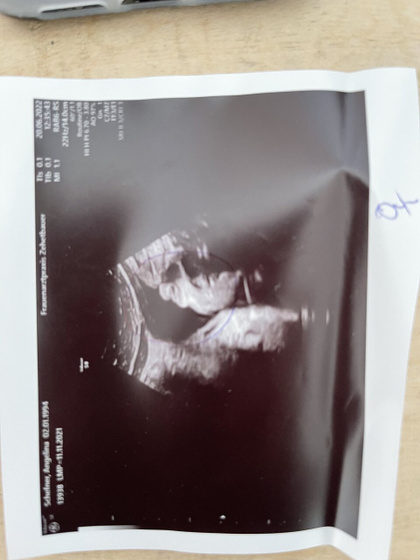

Всем приветик девочки кто помнит я задавала вопрос по поводу пола ребёнка и вот вчера была на последнем узи в 31 неделю ???ожидания наши были напрасны у нас 4 девочка врач сказала 100% (фото узи приложила наш пирожок??)не знаю как настроить себя правильно я рада что все хорошо доченька здорова и т.д Но понимаю что муж хочет сына ещё, уже начинаются разговоры на эту тему а я устала не хочу больше рожать ???как с ним поговорить не знаю, для меня пол не важен вообще но из за мужа у меня уже фобия какая то хоть волком вой???ещё не родила а уже стресс у меня?

Здравствуйте это блок для беременных и здесь все выкладывают свои узи и делятся опытом я не вижу в этом ничего неприличного .

Тоже выкладывают и обсуждают и сравнивают и просят чтобы сравнить со своим как выглядит.И в интернете хватает и пирожков и писюнов детей да и мамочек в лифчике и трусах со своими животиками ,21 век на дворе в этом ничего такого нет если вы против такого то просто не смотрите и не заходите на такие форумы )))это выбор каждого.удачи вам

Пирожок конечно очень видно ?

Это да не спутаешь???